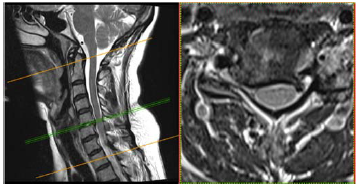

Uma paciente de 47 anos de idade apresenta quadro de cervicobraquialgia direita há cerca de três meses, associada a parestesia no membro superior direito, que se estende até a mão, principalmente nos dedos indicador e polegar. Ao exame físico, nota-se leve redução do reflexo braquioestilorradial. O teste de Spurling foi positivo à direita. Observou-se ausência de paresias.

No citado caso clínico, foi solicitada uma ressonância magnética cervical, conforme representado nas figuras. Esse exame evidencia uma

Uma paciente de 47 anos de idade apresenta quadro de cervicobraquialgia direita há cerca de três meses, associada a parestesia no membro superior direito, que se estende até a mão, principalmente nos dedos indicador e polegar. Ao exame físico, nota-se leve redução do reflexo braquioestilorradial. O teste de Spurling foi positivo à direita. Observou-se ausência de paresias.

No caso clínico relatado, o seguimento vertebral afetado é o

Uma paciente de 47 anos de idade apresenta quadro de cervicobraquialgia direita há cerca de três meses, associada a parestesia no membro superior direito, que se estende até a mão, principalmente nos dedos indicador e polegar. Ao exame físico, nota-se leve redução do reflexo braquioestilorradial. O teste de Spurling foi positivo à direita. Observou-se ausência de paresias.

Nesse caso clínico, a provável raiz acometida é a raiz de